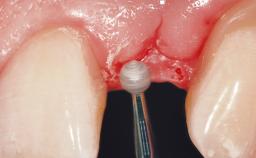

A 29-year-old female patient presented for treatment to replace the upper left central incisor tooth with an implant- supported restoration. The tooth had been intermittently symptomatic for the previous 12 months. The tooth had originally suffered trauma about 15 years previously. Several endodontic treatments had been performed, including an apicectomy procedure to retain the tooth. The patient was healthy and a non-smoker. She had reasonable expectations in regard to esthetic outcomes and the risk of marginal tissue recession following treatment. At medium smile, the gingival margins of the upper teeth were visible, with a display of 3 to 4 mm of the gingival margins. Gingival recession of tooth 21 and a discrepancy in the gingival levels between teeth 11 and 21 was observable during normal speech and smile.

Placement Protocol Immediate implant placement

Tooth Site Maxillary incisor or canine

Socket Morphology Single-root socket

Socket Integrity Damage to one or more bone walls

Bone Volume Damage to one or more socket walls